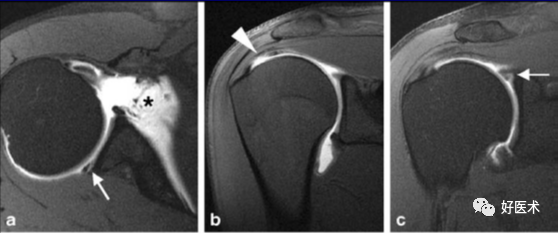

3)完全性撕裂

原发征象:肌腱局部缺如,连续性液体信号横贯肌腱的全层,这使得盂肱关节和肩峰下滑囊相通。

继发征象:

①肩峰下滑膜囊积液,积液在T1WI /PDWI上呈中等信号,T2WI+FS上呈高信号;

②冈上肌肌肉、肌腱结合处回缩(正常位置在肱骨头上方);

③滑囊旁脂肪垫的渗出丢失。

MR 关节造影:局限性或弥漫性充满造影剂的裂隙贯穿肌腱全层,肌腱失去其连续性。

正常、异常肩袖肌腱和邻近软组织结构的MR表现

冈上肌肌腱撕裂可分为全层或部分,部分撕裂又分为下表面(关节面)撕裂、上表面(滑囊侧)撕裂及腱内撕裂。据文献报道,冈上肌肌腱下表面撕裂最常见,可为上表面撕裂的2~3倍,腱内撕裂则最少见。

冈上肌腱不完全撕裂

冈上肌腱不完全撕裂伴肩峰下囊积液